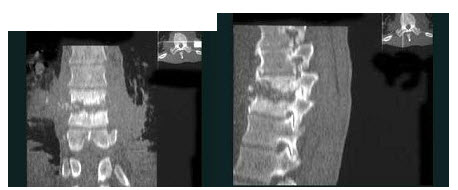

女,59岁,腰背部疼痛伴低热乏力,结合影像学检查,最可能的诊断是()

A.脊柱转移瘤

B.化脓性脊柱炎

C.脊椎结核

D.椎体压缩骨折

E.强直性脊柱炎